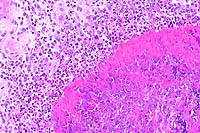

2x

obj

- Case 12-2. Lymph node. Extensive necrosis and inflammation

with focal areas of hemorrhage.

40x

- Case 12-2. Lymph node. Multifocally within zones suppuration

and necrosis, are multiple large colonies of bacteria.

obj, Brown & Brehn

- Case 12-2. Perinodal fat. Brown & Brehn staining

reveals that bacterial colonies are composed of short reddish-blue

(Gram negative) rods.

- AFIP Diagnosis: Lymph node: Lymphadenitis, necrotizing,

suppurative, diffuse, severe, with numerous bacilli, Siberian

polecat x black-footed ferret (Mustela eversmanni x M. nigripes),

mustelid.

- Note: Necrosis, suppurative inflammation and hemorrhage

are present within the surrounding perinodal tissues in some

sections.